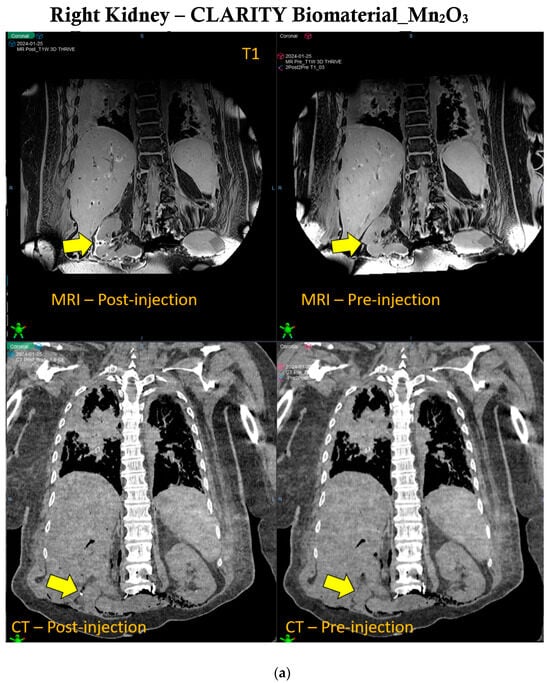

Manganese oxide offers significant multi-functionality in the CLARITY biomaterial, providing both CT and MRI contrast over time during radiotherapy. Figure 3 shows that the contrast provided by manganese oxide nanoparticles is brighter in MR images and lasts beyond the 30 days of observation, as opposed to the CT contrast provided by these same nanoparticles. However, Supplementary Figure S2 shows CT contrast for up to 30 days post-treatment. Human cadaveric specimens were used to further evaluate the CT and MRI contrast provided when the CLARITY biomaterial was formulated with Mn2O3 and injected into the right kidney of the specimen, as indicated by the yellow arrow shown in Figure 4a. CLARITY biomaterial formulated with cerium oxide interestingly also showed both CT and MRI contrast in the breast tissue of the specimen, as shown in Figure 4b. An additional functionality of the manganese oxide nanoparticles is the potential to address hypoxia, which is critical for enhancing radiotherapy and overcoming immunosuppression [28,29,30,31].

Figure 4.

IGRT capability of CLARITY biomaterial in Human Cadaver. (a) The right kidney of the human cadaver specimen is showing CT and MRI (T1-weighted) contrast after being inoculated with CLARITY biomaterial formulated with manganese oxide nanoparticles, as shown by the yellow arrow. (b) The breast tissue is showing similar CT and MRI (T2-weighted) contrast post-injection of the CLARITY biomaterial formulated with cerium oxide nanoparticles, as indicated by the yellow arrow.

2.6. MRI and CT Acquisition for the Human Cadaver

To further assess the feasibility of the CLARITY biomaterial in providing image guidance, contrast imaging was conducted in a human cadaver approved by the Johns Hopkins Institutional Review Board (IRB) under protocol # NA_00070589 (PI KD). The source of the human cadaver involved in our research is the State of Maryland Anatomy Board. As an academic center, we can send requests to get and then later return the cadaver from the State of Maryland Anatomy Board for medical education and research. Please see this link https://health.maryland.gov/anatomy/Pages/EducatorsResearchers.aspx (accessed on 25 July 2024) for more information. A refrigerated, unfixed cadaveric specimen was implanted in 2 regions: (a) the right kidney, with 3 mL of the CLARITY biomaterial formulated with manganese oxide nanoparticles, and (b) the breast, with 3 mL of the CLARITY biomaterial formulated with cerium oxide nanoparticles. CT simulation (TOSHIBA Helical CT scan with 2 mm slice thickness, 120 kVp, and X-ray tube current of 100 mA) was done with the cadaveric specimen in the supine position. The human cadaver specimen was subsequently imaged again. A Philips Achieva 3.0 T MRI System with BODY Transmit Coil was used for MRI acquisition with a repetition time of 5.31 ms, a flip angle of 100, a percent phase field of view of 70.833, and a slice thickness of 0.9 mm. CT and MR imaging were done before and after injection of the CLARITY biomaterial formulations.